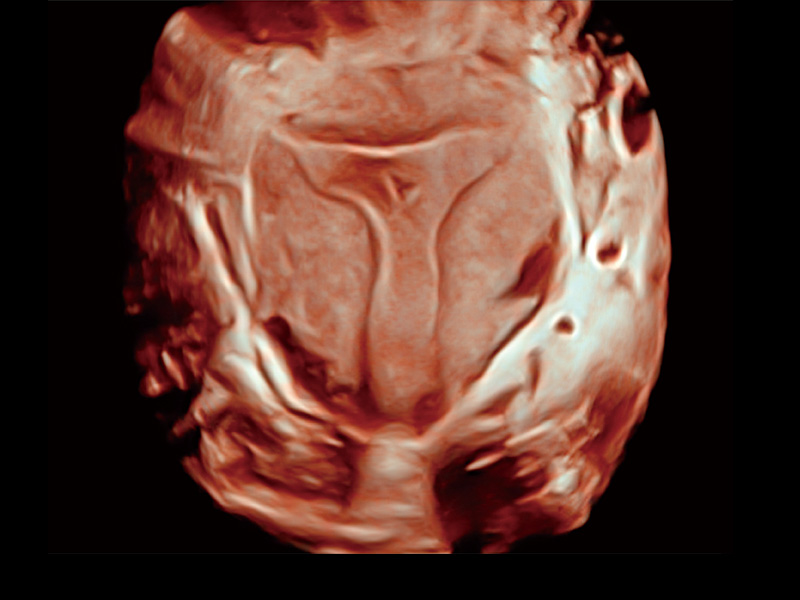

卵巢多囊样改变

单角子宫